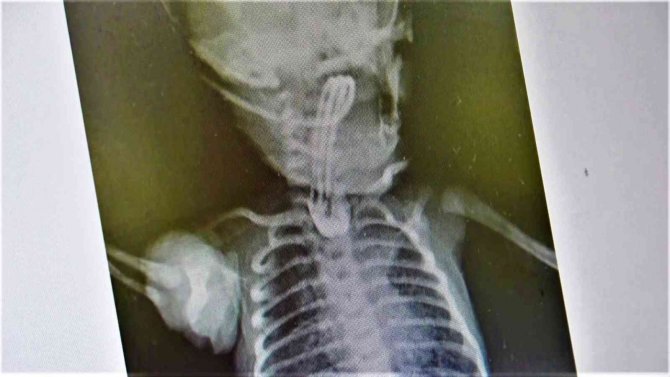

Samsun'da tıp dünyasında nadir gözüken durumlardan biri yaşandı. Murat (27) ve İlknur (26) Kaya çiftinin ilk bebekleri olan Erva Kaya, yemek borusu olmadan dünyaya geldi. Erken müdahale edilmezse sonucu ölüm olan durum karşısında aile, VM Medical Park Samsun Hastanesi'nde görev yapan Çocuk Cerrahisi Uzm. Opr. Dr. Ayşe Bahar Edirne'ye ulaştı. Uzm. Dr. Edirne, bebeğin 3 santimetre olan yemek borusunu ameliyatla 15 santimetreye çıkararak hayatını kurtardı.

Bebeğin tedavisi hakkında bilgi veren Uzm. Dr. Edirne, "Bebeğimiz doğduğunda yapılan ön tetkiklerde yemek borusunun olmadığı anlaşıldı. 2-3 günlük olduktan sonra ameliyatını gerçekleştirdik. 15 gün sonrasında da ağızdan beslemeye başladık. Yemek borusunun oluştuğunu çekilen filmlerde tetkik ettik. Sonrasında da ailesinin yanına verdik. Kontrolleri yapıldığında ise hiçbir problemi olmadığı görüldü. Eğer bu hastalık tespit edildiğinde zamanında tedavi edilmezse yemek borusu olmadığı için bebeğin beslenme şansı olmuyor. Ondan sonra da maalesef yaşama şansı olmuyor. Bu hastalık acil tedavi edilmesi gereken bir sorun. Öncelikle ultrason ve ön tetkikler yapılıyor. Bütün hazırlıklar yapıldıktan sonra özellikle yeni doğan yoğun bakımın olduğu bir donanımlı bir hastanede bakımının yapılması gerekiyor. Ameliyat da başarılı geçtiği takdirde bu şekilde doğan bebekler hayata tutunuyorlar. Ameliyat yapılmazsa yaşama şansı olmayan bir hastalıktır. Binde bir ihtimalle karşımıza çıkıyor" dedi.